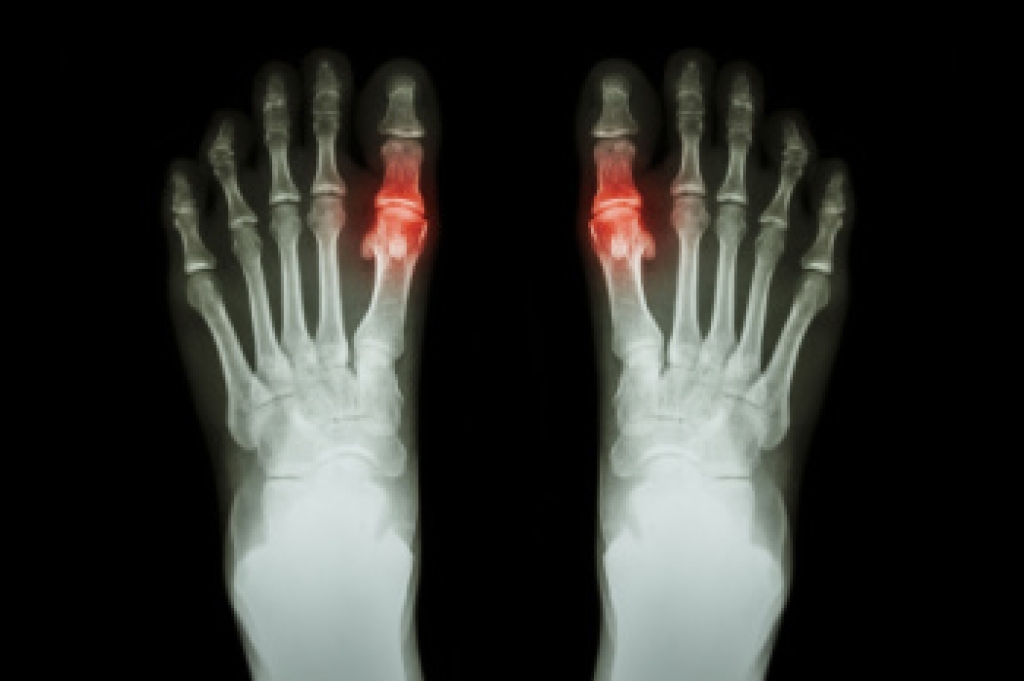

Preventing falls, especially in older adults, is essential for maintaining health and independence. As people age, factors such as muscle weakness, balance issues, and certain medical conditions can increase the likelihood of falls. Certain lifestyle changes can significantly reduce this risk. Regular exercise that focuses on strength, balance, and endurance is a key factor in preventing falls. Strengthening the core and legs improves stability, while activities like tai chi and yoga enhance balance. Further, ensuring that your home is free of hazards, like loose rugs or poor lighting, can create a safer environment. A podiatrist plays a vital role in fall prevention by assessing and addressing foot-related issues, which are often overlooked but critical for maintaining proper gait and balance. Custom orthotics, footwear recommendations, and treatment for any underlying foot problems can help reduce the risk of falls in older adults. If you have endured a foot injury from falling, it is suggested that you schedule an appointment with a podiatrist for treatment and fall prevention strategies.